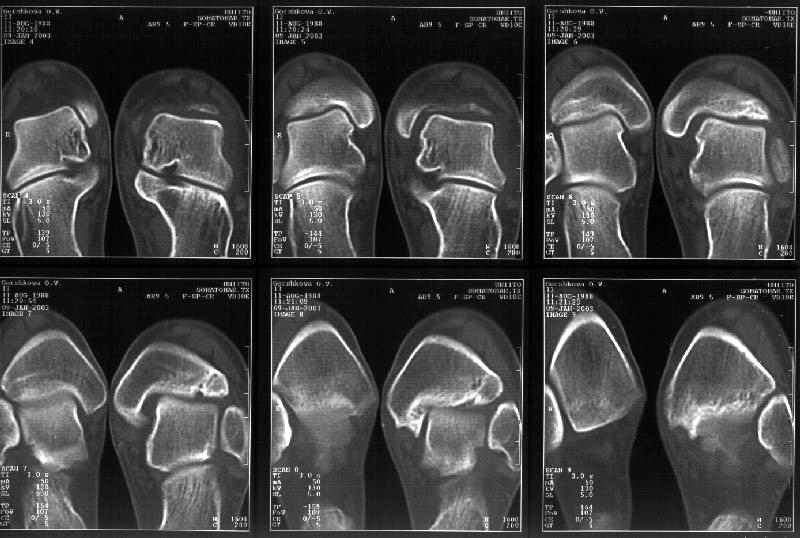

Сегодня пациентке сделали сравнительную КТ. А ксиальные и Фронтальные срезы приложены. Ваше мнение?

Фронтальные

Аксиальные

Спасибо за КТ -она изумительная. К сожалению, я по дороге на врачебный викенд на Мёртвом море и не смогу подготовить комментарий и схемку до 19.01.03 Помоему, результат КТ даёт чёткую возможность красивой и эффективной помощи.

Отправитель: Й. Воск 19 Январь 2003, 22:50

На КТ я попытался изобразить скромными своими способностями (А)- место перелома, (С)- нормальный суставной зазор меж тараном и тремя его маллеолами. (В)- образовавшийся в результате перелома широкий раза в три зазор, позволяющий, по-моему, сублюксацию тарана при ходьбе. В свете данных КТ, критически важных, я бы предложил вертикальную остеотомию места перелома

задне-внутренним подходом и фиксацию мед. маллеола прижатым к тарану с помощью тонкого compression screw. После этого гипсовый сапожок и немедленное расхаживание ноги.